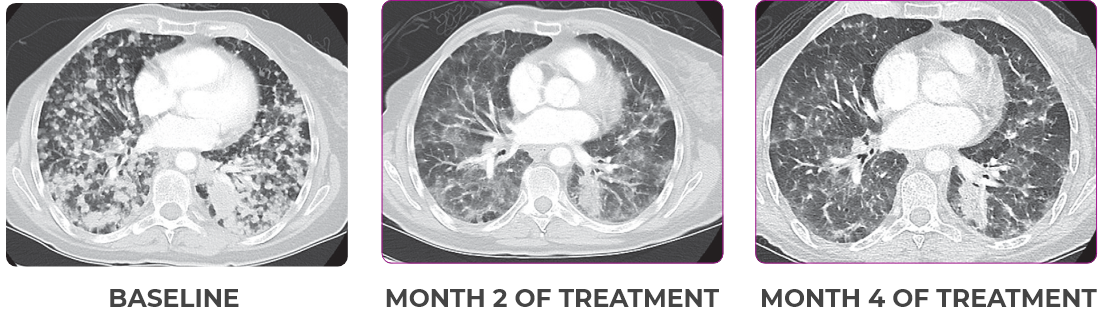

PATIENT CASE:

METASTATIC NSCLC1,a

- 30-year-old female

- Progression on first-line doublet chemotherapy

- PRa after 6 weeks of treatment with VITRAKVI® (larotrectinib)

- Complete clinical response achieved by 12 months with residual scarring

VITRAKVI treatment1

- VITRAKVI 100 mg twice daily orally

Response to VITRAKVI1

- Partial response and symptom improvement confirmed by chest X-rays after <1 month of treatment

- Imaging performed 6 weeks into treatment revealed considerable decrease in the size of both target lesions

- No treatment-related AEsa were reported

- Patient was symptom free and remained on VITRAKVI

Response in primary and metastatic lesions1

Lung imaging of primary tumors.

SCAN 1: LUNG

SCAN 2: LUNG AND BONE

Images courtesy of Dr Maximilian Hochmair.

aNSCLC, non-small cell lung cancer; PR, partial response.